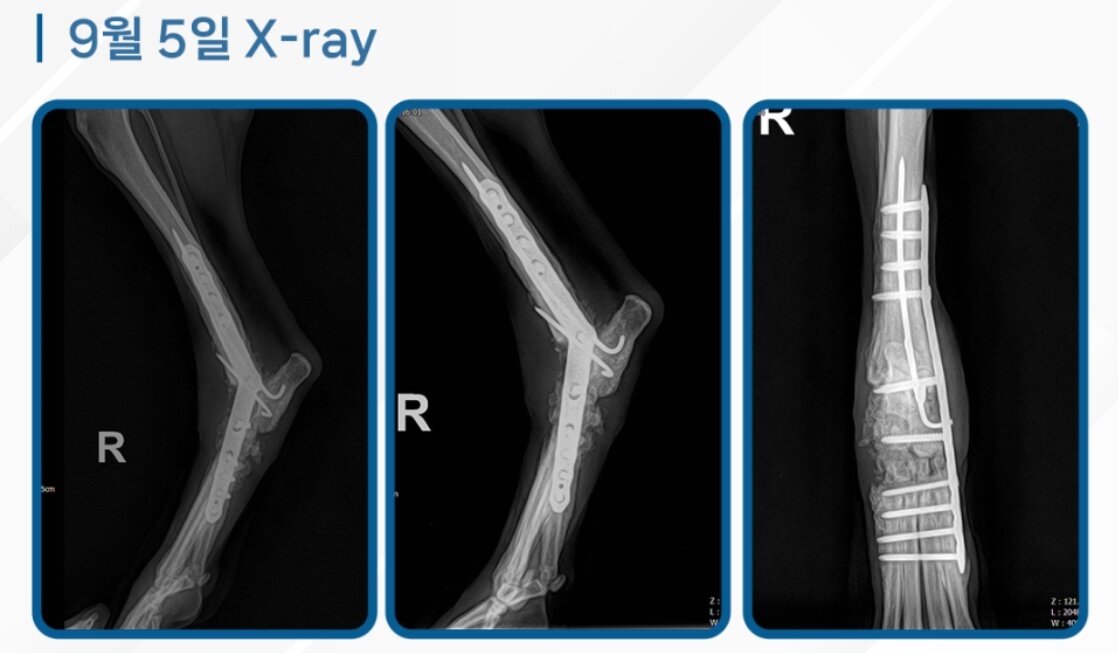

본문 이미지 - 관절고정술 후 파랑이의 엑스레이 영상(로얄동물메디컬센터 제공) ⓒ 뉴스1

관절고정술 후 파랑이의 엑스레이 영상(로얄동물메디컬센터 제공) ⓒ 뉴스1